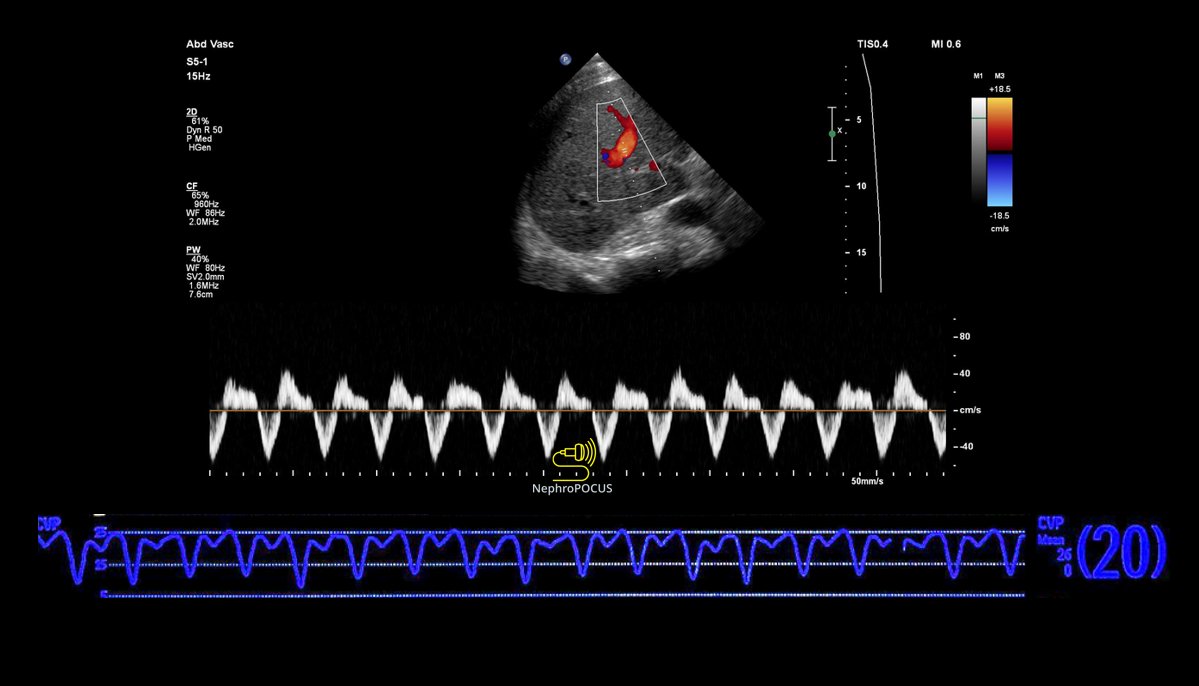

51-year-old woman with a history of rheumatoid arthritis. Progressive dyspnea in the last 4 years. I need help with hepatic venous flow pattern. #echofirst